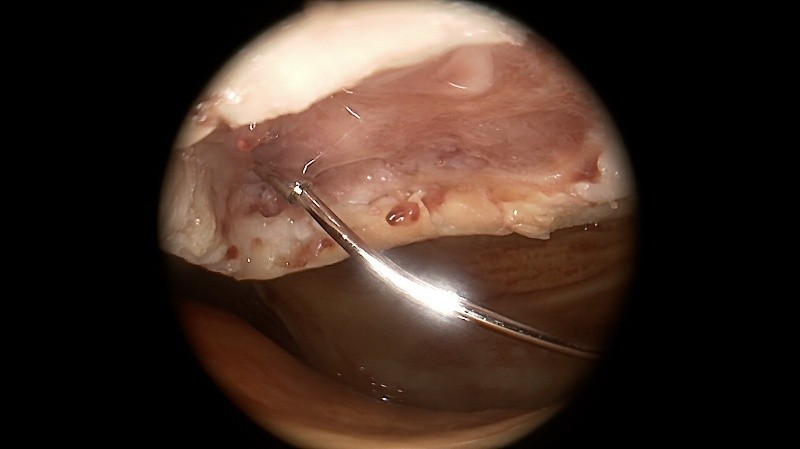

Meniskus

Der Meniskus fungiert als „Stoßdämpfer“ zwischen Oberschenkel und Unterschenkel, verbessert die Kongruenz der Gelenkpartner und trägt zusätzlich zur Stabilität des Kniegelenkes bei. Je nach Rissform, Patientenalter, traumatischer oder degenerativer Ursache bestehen unterschiedliche Behandlungsoptionen von konservativer Therapie bis hin zur operativen Versorgung mittels Teilresektion oder Meniskusnaht. Bei speziellen Meniskusverletzungen (z.B. der sogenannten Wurzel-Läsion) kann – um den Einheilungsprozess zu gewährleisten – auch ein Zusatzeingriff wie eine Umstellungsosteotomie bei O-Beinen nötig werden.

Bei jungen Patienten mit Meniskusverlust besteht auch die Möglichkeit einer sog. Meniskustransplantation, um langfristig das Fortschreiten der Arthrose hinauszuzögern. Hierbei wird aus einer Spenderbank ein bzgl. Größe und Form passender Spendermeniskus ausgewählt und nach Entfernung des defekten Eigenmeniskus im Gelenk fixiert.